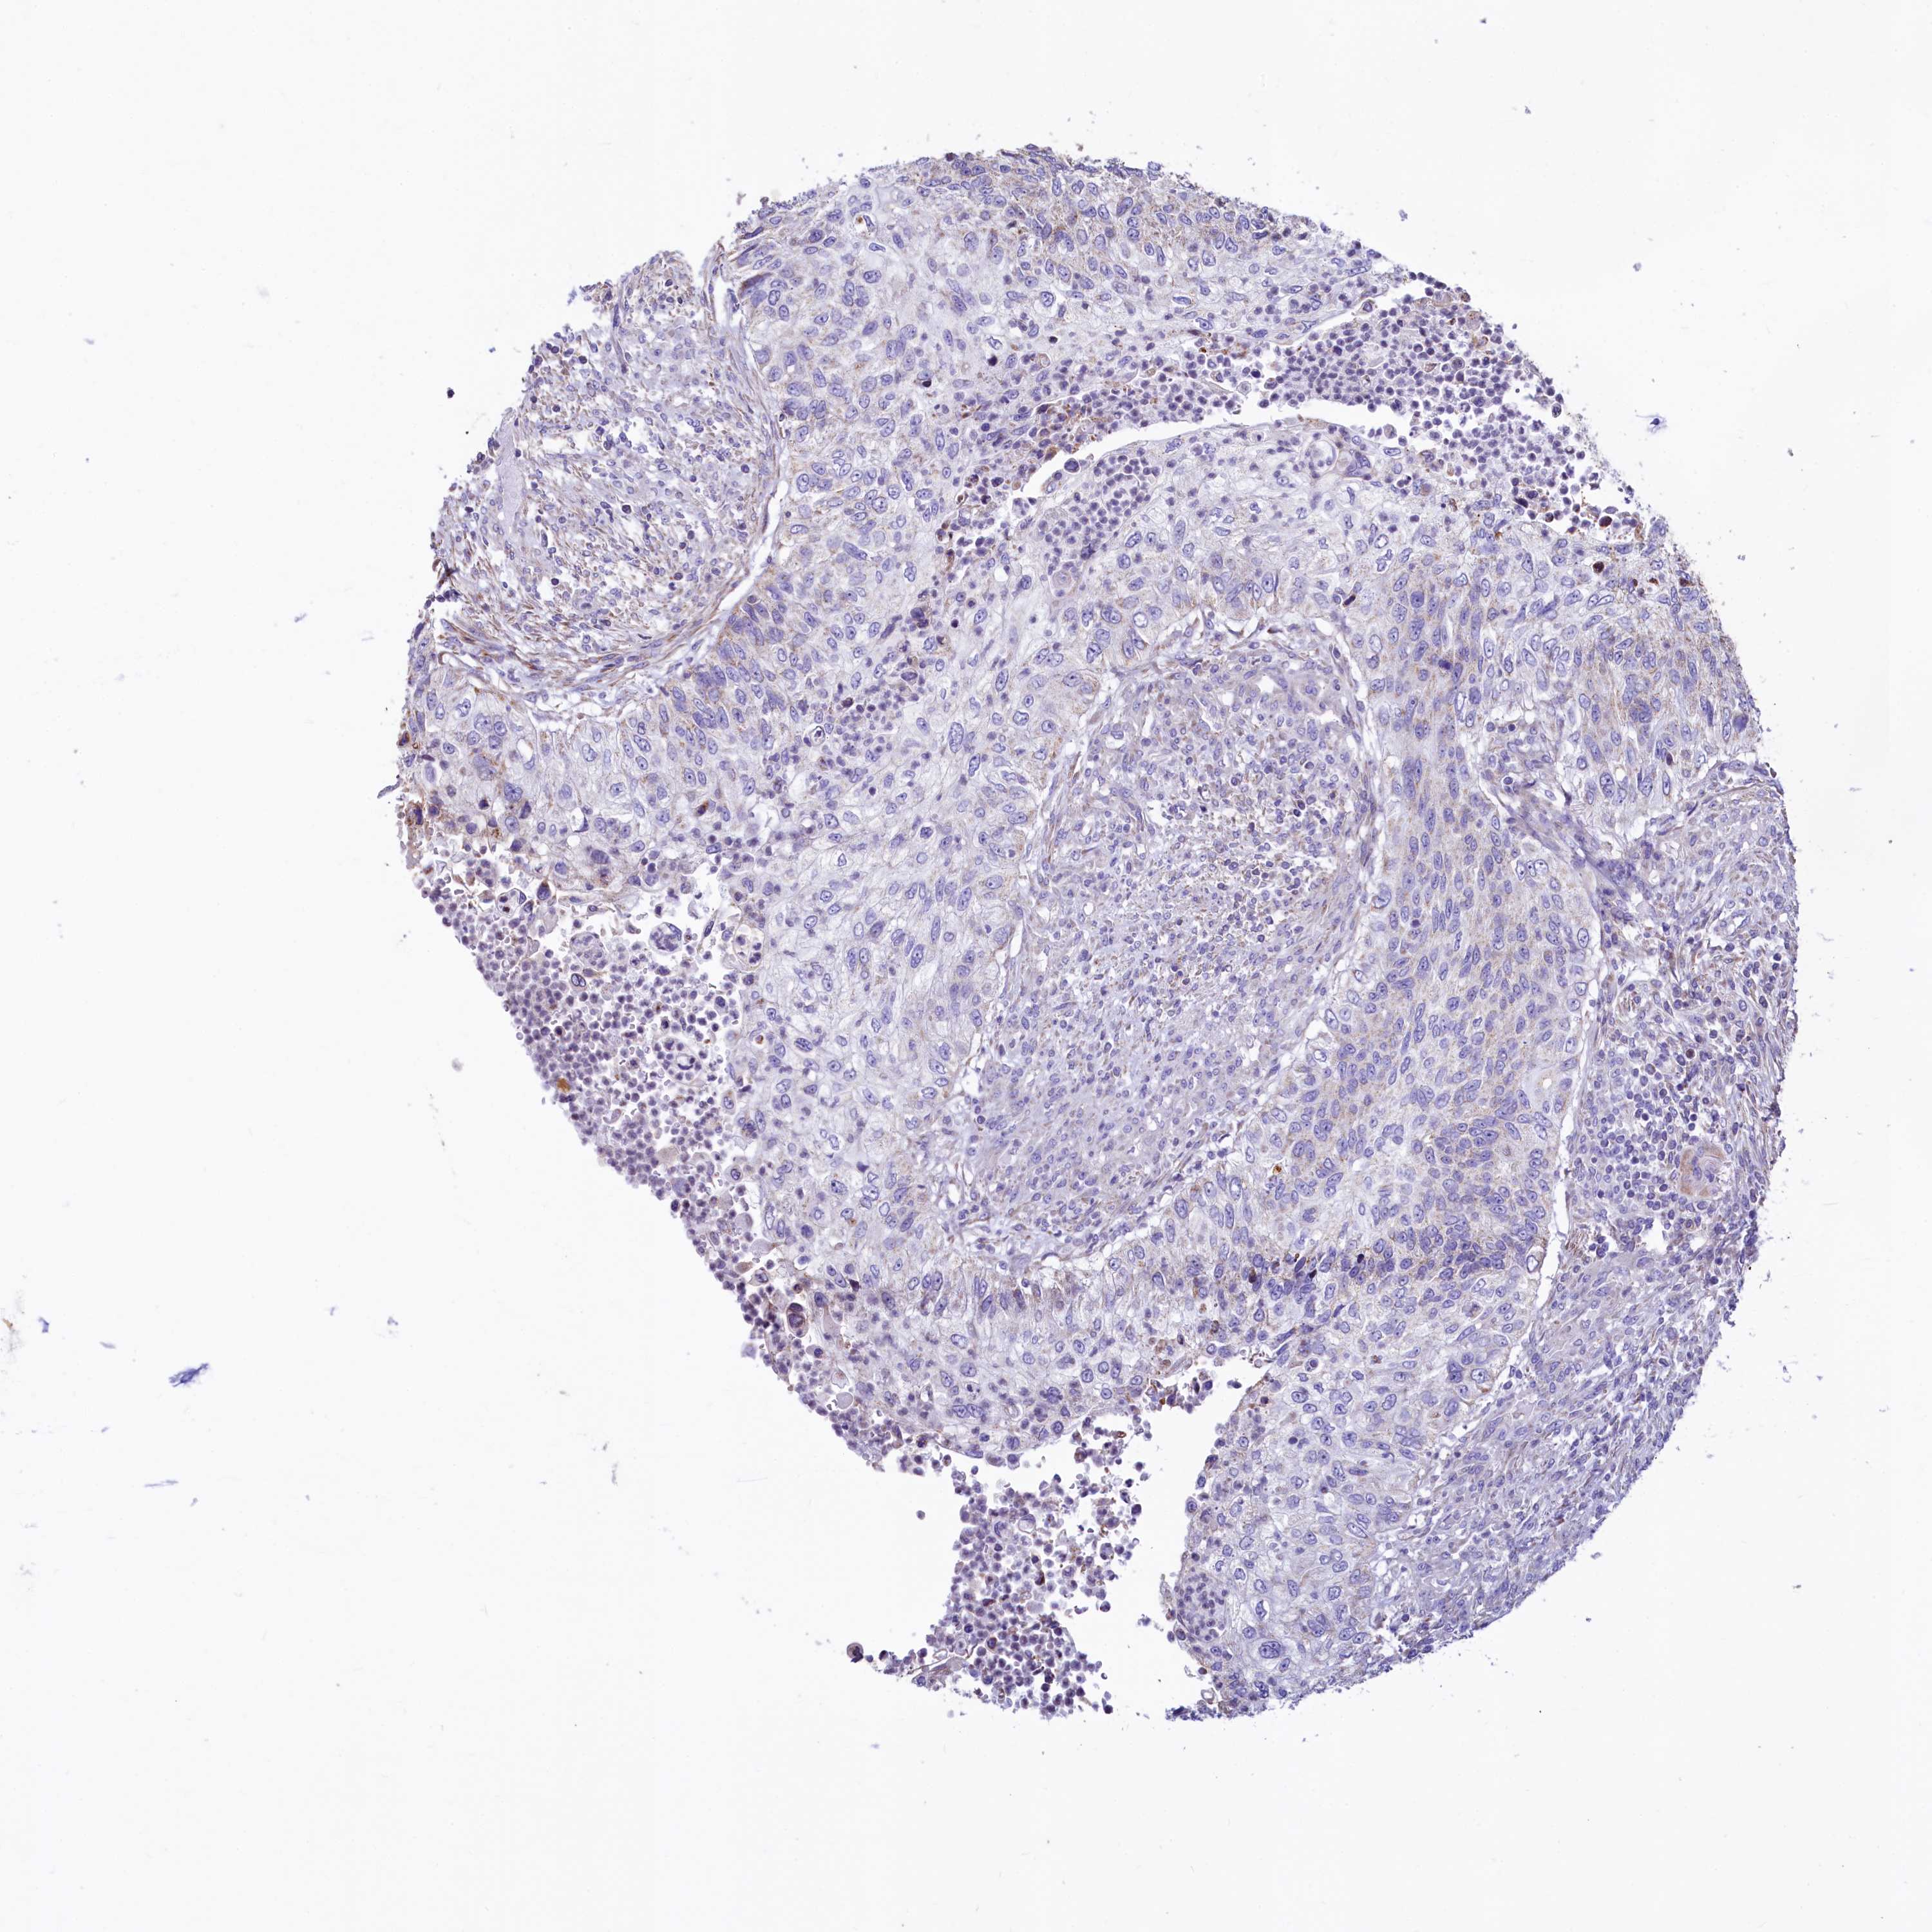

UROTHELIAL CANCER - Protein expressioni

A mouse-over function shows sample information and annotation data. Click on an image to view it in a full screen mode. Samples can be filtered based on level of antibody staining by selecting one or several of the following categories: high, medium, low and not detected. The assay and annotation is described here.

Note that samples used for immunohistochemistry by the Human Protein Atlas do not correspond to samples in the TCGA dataset.

Antibody stainingi

Antibody staining in the annotated cell types in the current human tissue is reported as not detected, low, medium, or high, based on conventional immunohistochemistry profiling in selected tissues. This score is based on the combination of the staining intensity and fraction of stained cells.

Each image is clickable and will lead to virtual microscopy that enables deeper exploration of all samples and also displays staining intensity scores, fraction scores and subcellular localization as well as patient and tissue information for each sample.

Antibody HPA040401

Antibody HPA043921

Urothelial carcinoma, High grade

Urothelial carcinoma, Low grade

Urothelial carcinoma, NOS